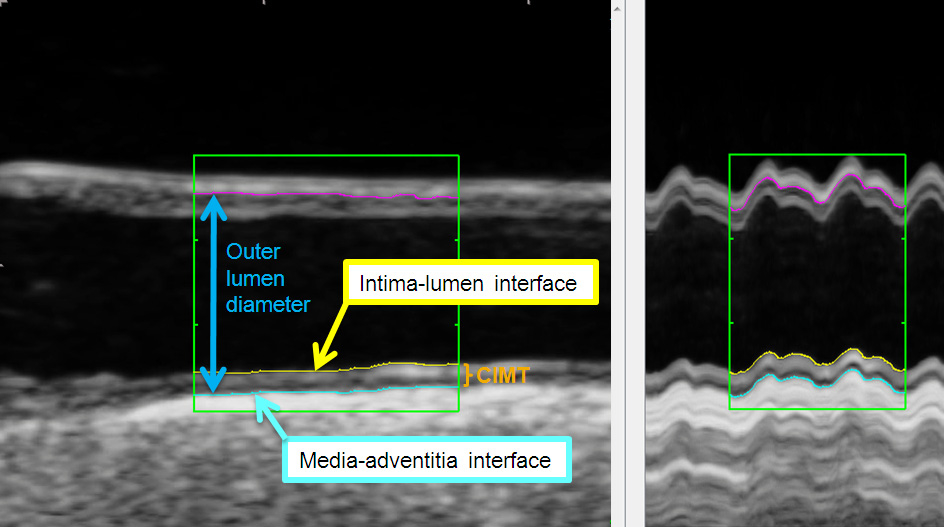

a)  CIMT is defined as the viewable distance between the lumen-intima- and the media- adventitia interface (see fig. 1).

Figure 1

Ultrasound image of the common carotid artery (longitudinal axis) with tracing lines of automatic contour-detection at the lumen-intima- (yellow line) and the media- adventitia interface (blue line). Outer lumen diameter (between blue- and pink-coloured line) in the common carotid artery in B-mode (left) over two heart cycles and with M-mode (right) generated by 180 single images of a this clip. The mean CIMT at the far wall was 0.87 mm.

Originally, CIMT-measurements were performed via a manual method that could be integrated in ultrasound systems or per additional acquired software. However, the last few years it could be demonstrated that this method is associated with a higher reader-subjectivity compared to automatic or semiautomatic (automatic + manual correction) measurement software [21]. These can be implemented in the ultrasound system or can base a) on an image-analysis (contour-detection) (fig. 1, [22]) or b) on the analysis of radiofrequency signals. The radiofrequency – analysis is performed with single images or continuously over more heart cycles.